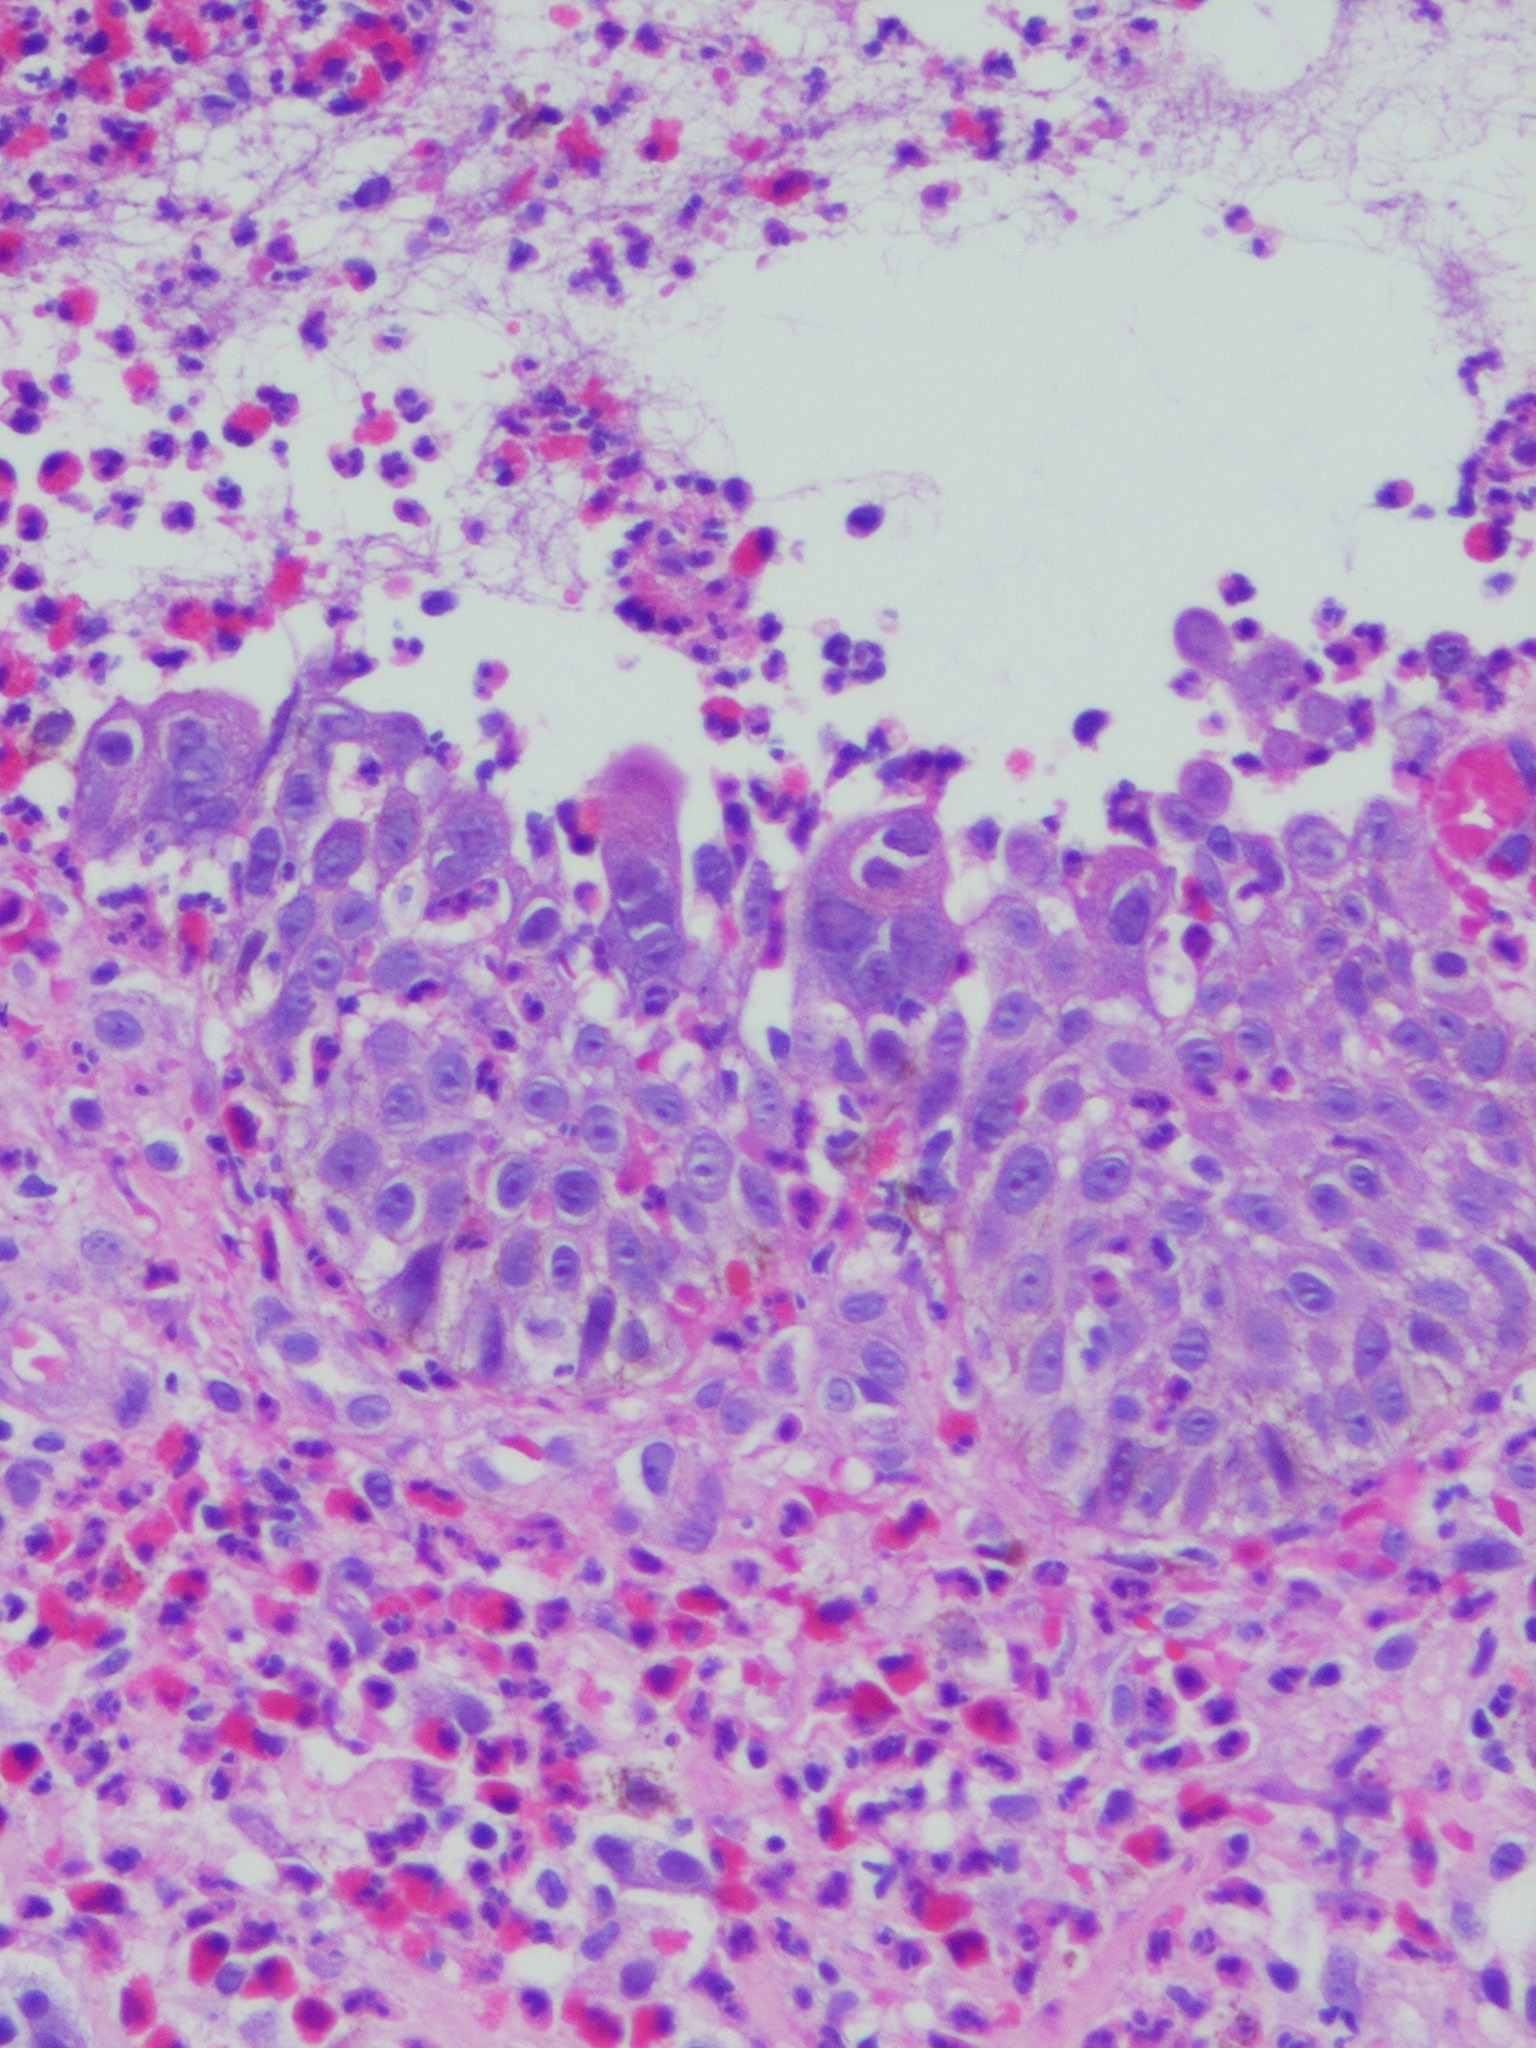

Herpes simplex = العقبول البسيط